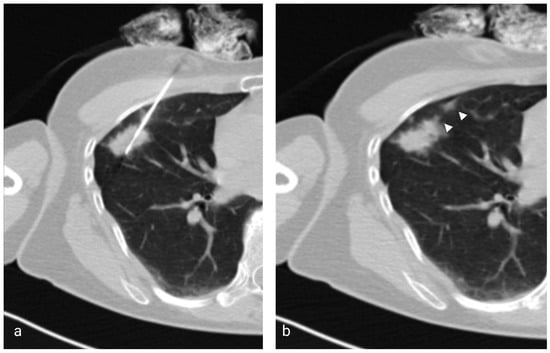

Figure 1.

(a) Axial low-dose CT showing the 17G coaxial needle and the 18G biopsy needle within a right middle lobe mass. (b) Image taken immediately after the injection of saline solution and removal of the coaxial needle showing the hyperattenuating needle tract (arrowheads).